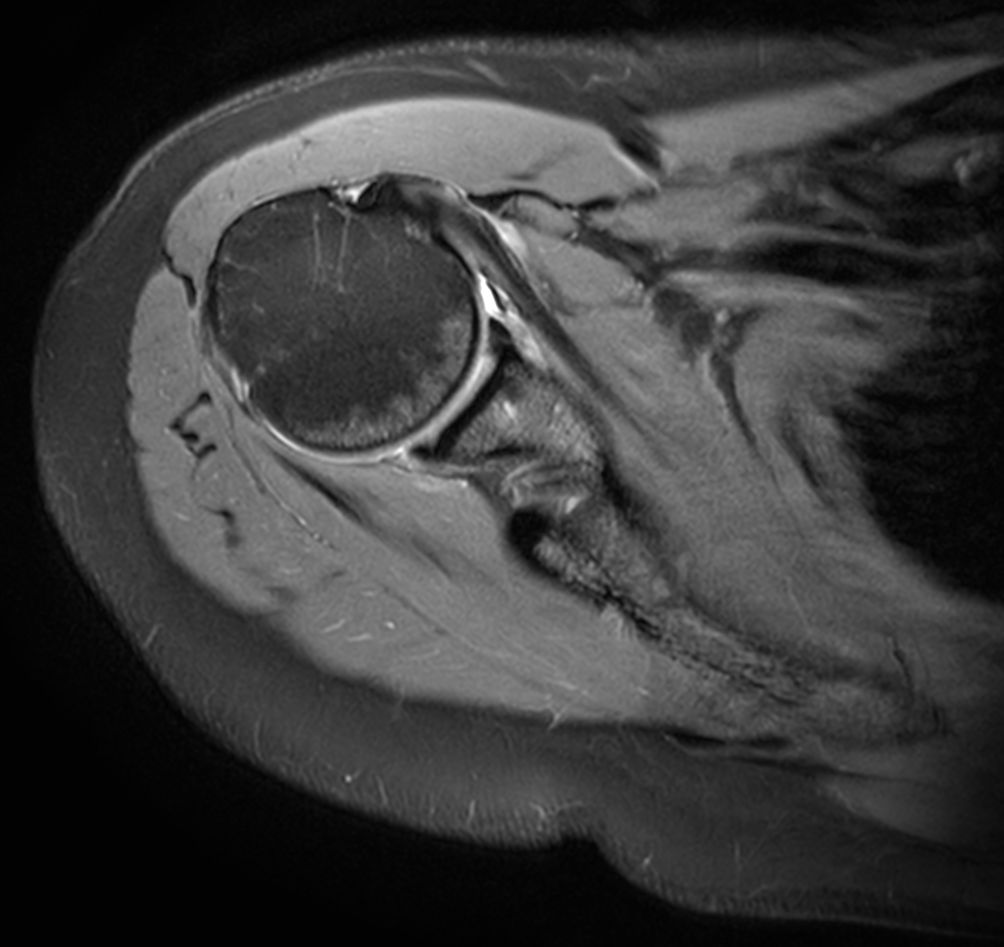

Sagittal T2w TSE